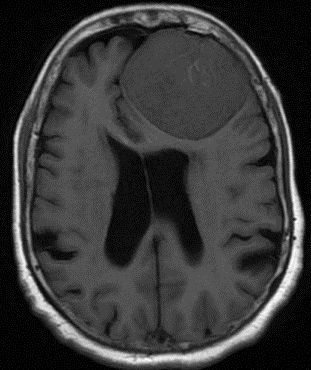

Brain PET and age may help clinicians determine which patients with amnestic mild cognitive disorder may progress on to probable Alzheimer’s disease.